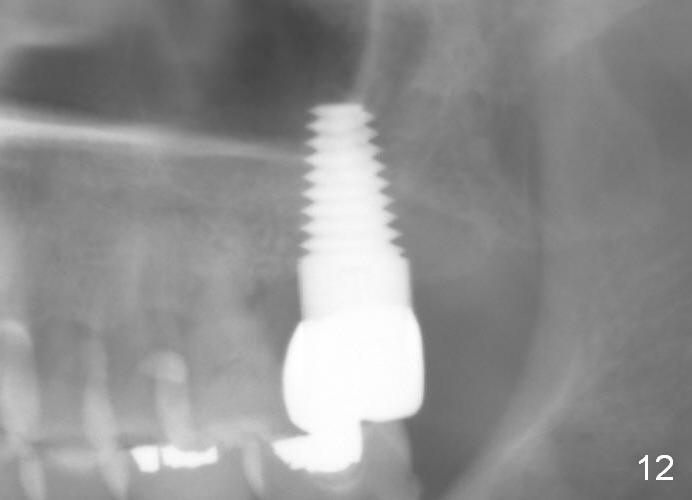

Model study shows that the implant is placed distally (Fig.9,11) in addition to buccal implant exposure (Fig.10 arrowheads). Postop, the patient complains of upper left discomfort, which is more likely associated with furcal infection of the tooth #14. The symptom disappears after use of water pik. Panoramic X-ray is taken 6 months post cementation (Fig.12).